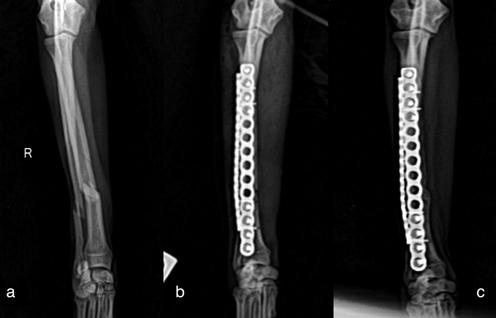

ocupa, además de las radiografías postoperatorias realizadas tras la cirugía correctiva y las efectuadas antes de retirar los implantes, se realizó una TC de revisión tras la extracción de los mismos (al año y dos meses de su colocación), observándose en 3D una buena remodelación y alineación de los huesos. Si comparamos estas imágenes de TC con las primeras, es decir, con las de la planificación quirúrgica antes de la corrección, se puede observar que la superposición de ambas TC muestra una alta precisión en lo que respecta al resultado obtenido (Fig. 8).

Figura 8. (A) Reconstrucción en 3D de los huesos del antebrazo afectado antes de realizar la ostectomía y colocar los implantes y (B) después de retirarlos.